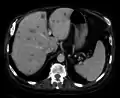

| Axial CT of the abdomen showing multiple liver metastases | |